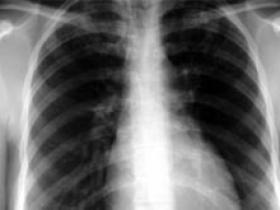

Aunque compromete en mayor medida a los pulmones, el grado de diseminación de la patología puede variar de un nivel mínimo a una invasión masiva, estado que empeora progresivamente si no se sigue la terapia correcta. Asimismo, el tratamiento incompleto de la enfermad, como por ejemplo, no tomar los medicamentos durante el tiempo prescrito, puede contribuir a la aparición de cepas de bacterias resistentes a la droga.